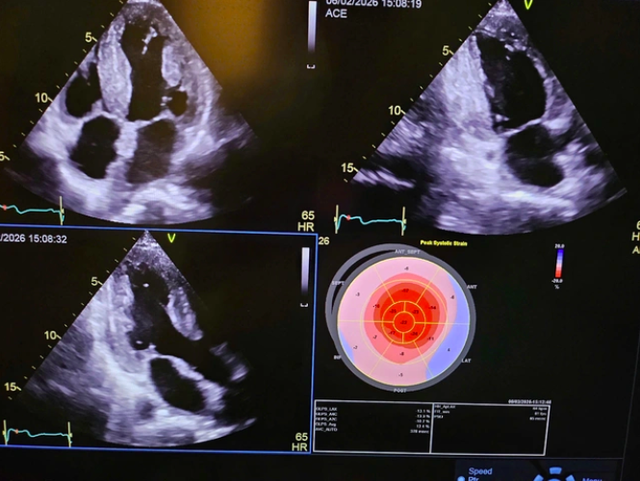

Bệnh nhân nam, 53 tuổi, được phát hiện mắc bệnh hiếm Amyloidosis di truyền thông qua quá trình chẩn đoán chuyên sâu tại Bệnh viện Việt Pháp Hà Nội. Nhờ các đánh giá lâm sàng, xét nghiệm di truyền và sinh thiết ở mức độ chi tiết cao, bệnh viện đã xây dựng được một hồ sơ bệnh án toàn diện, làm cơ sở quan trọng cho chiến lược điều trị.

Các bác sĩ chẩn đoán chuyên sâu về căn bệnh amyloidosis transthyretin di truyền – bệnh hiếm ảnh hưởng đồng thời tim và hệ thần kinh. Ảnh BVCC

Amyloidosis transthyretin di truyền là một bệnh hiếm do đột biến gen TTR, có thể gây ra suy tim, bệnh thần kinh ngoại biên, mất sức, hạ huyết áp tư thế đứng và nguy cơ tử vong sớm nếu không được phát hiện và điều trị kịp thời. Ảnh BVCC